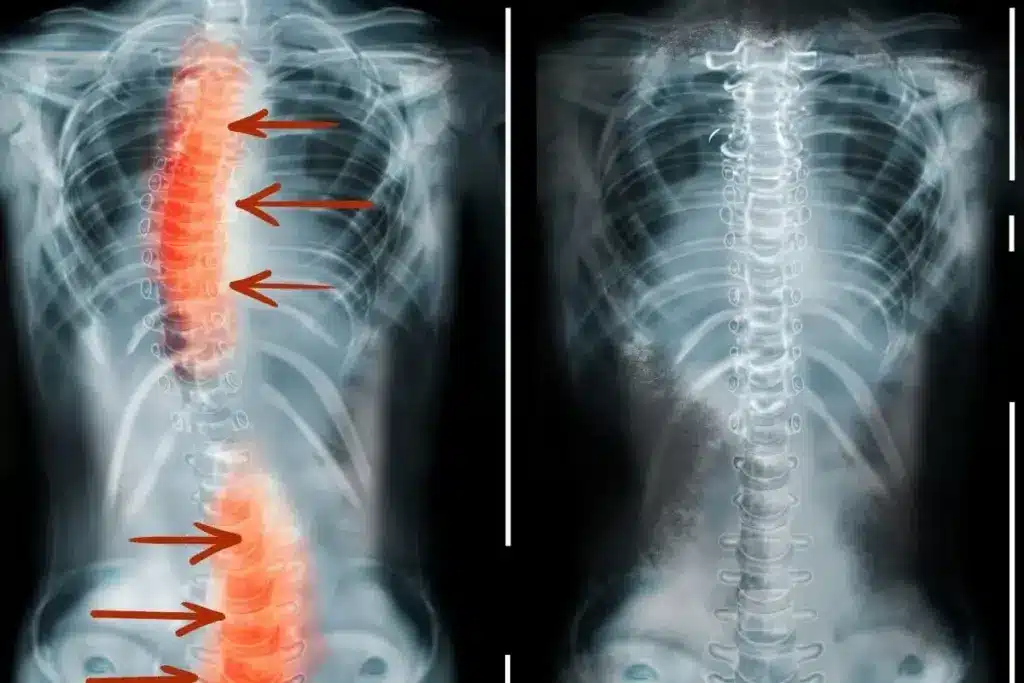

Diagnostic Approaches for Unspecified Spinal Curvature

Diagnosing unspecified spinal curvature needs a detailed approach. This includes clinical checks and advanced imaging. Early detection leads to better care and outcomes.

Imaging Techniques and Interpretation

Imaging is key in diagnosing spinal curvatures. We use X-rays, CT scans, and MRI to see the spine’s shape and any issues. These tools help us measure the curve and find any related problems.

Measuring Dextroconvex Curvature

Dextroscoliosis means the spine curves to the right. Accurate measurement is vital for treatment. The Cobb angle is a common method to measure this on X-rays.